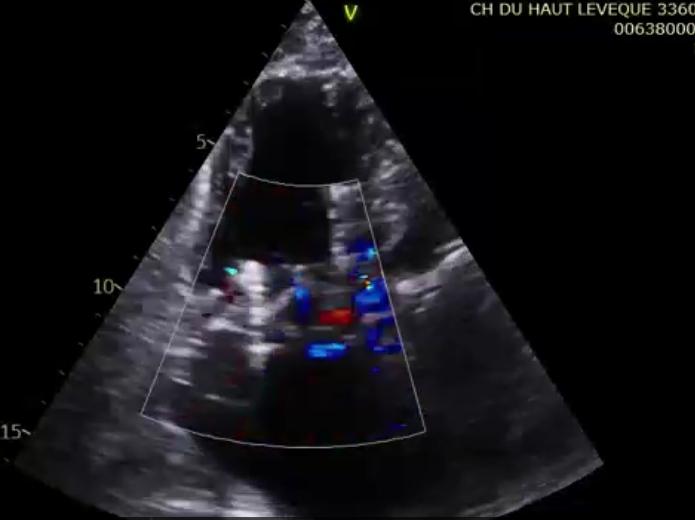

術前超聲提示極大量三尖瓣反流

術后超聲提示微量瓣周漏